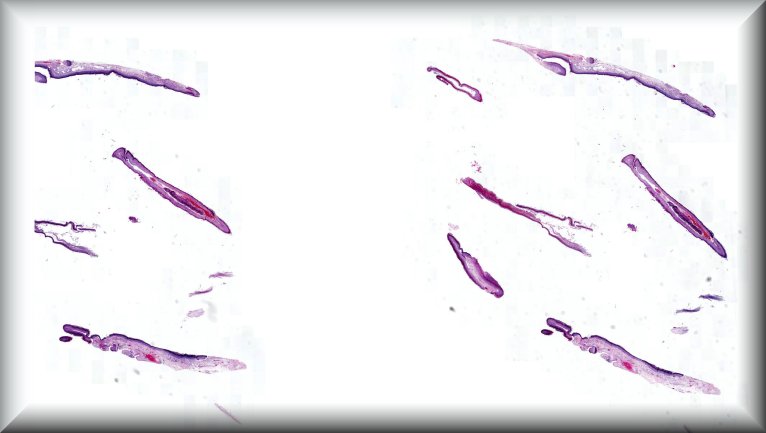

Claudia Auw-Haedrich: Vitreal opacities in a 56-year-old female with inherited Transthyretin amyloidosis. At the age of 41, our patient underwent a liver transplant due to hereditary transthyretin amyloidosis. Fifteen years later, she experienced visual deterioration to 0.5 in her left eye due to vitreous opacities. Protocol |